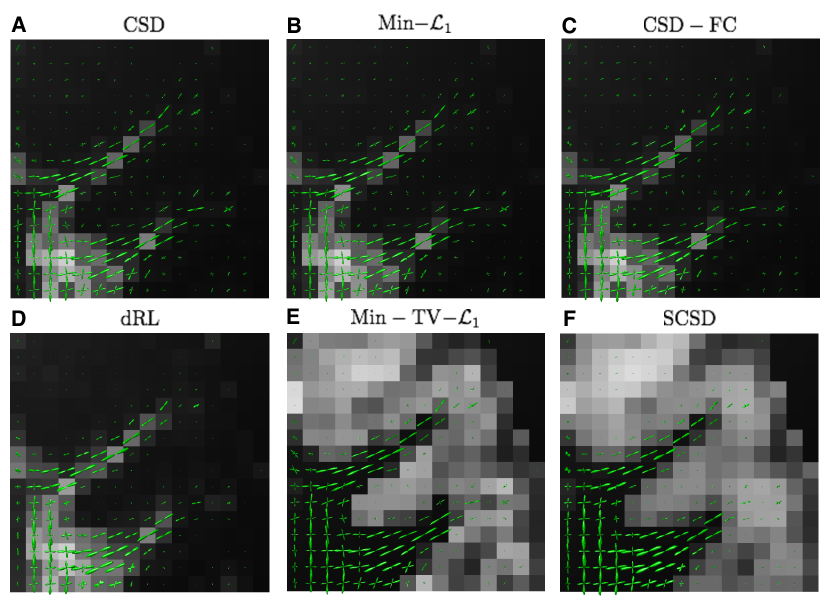

The reconstructions obtained for the same axial view and s/mm2 are depicted in Fig. 12, whose composition is identical to that of Fig. 10. Although fairly close in appearance to the previous case, these reconstructions allow us to make a number of important observations. First of all, as compared to the case of s/mm2, a wider bandwidth of the HARDI signals at s/mm2 leads to a better angular resolution, which is particularly noticeable in the case of dRL. Moreover, despite considerably worse noise conditions, the fODF reconstructions obtained by means of Min-TV- and SCSD have much less residual noise over the areas occupied by cortical grey matter, where isotropic diffusion is expected to prevail. This fact indicates the effectiveness of the regularization schemes exploited by these SD methods. Finally, a closer inspection of the glyphs in Fig. 12 reveals that the fODF reconstructions yielded by SCSD demonstrate a better spatial smoothness and anatomical consistency. The same observations can be made in the case of the coronal view, as shown in Figs. 13 and 14 for s/mm2 and s/mm2, respectively. (Note that the local region represented by these figures has been chosen according to the results in [44], which also provides indication of specific fibre bundles within the selected regions of interest).